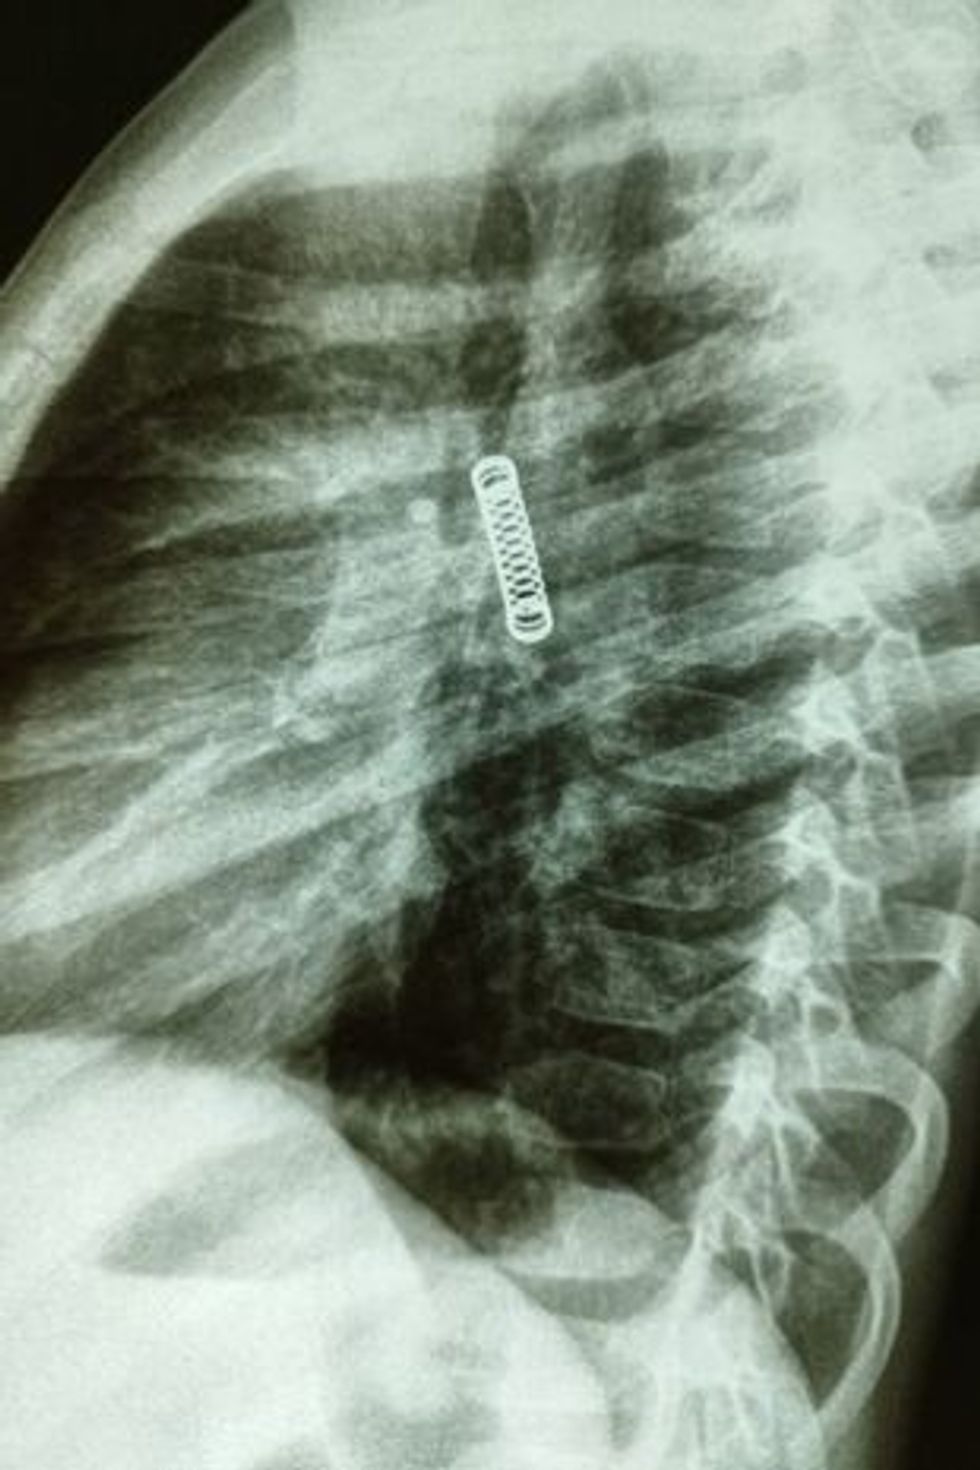

Një djalë të ri iu hoq një sustë metalike nga mushkëritë e tij, të cilën e kishte në trup gjatë tre muajve të fundit.

Ndërsa po kryenin kontrolle të gjera për të kërkuar shkakun e kollitjes së pandërprerë, mjekët u shtangën kur gjetën një objekt metalik në mushkërinë e majtë të djalit.

Dr Carlos Morinigo tha se procedura ishte e ndërlikuar pasi susta metalike kishte qëndruar në mushkëritë e djalit për një kohë relativisht të gjatë, si dhe dëmet që kishte shkaktuar gjatë asaj periudhe.